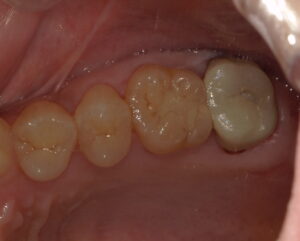

患者さんは30代女性。症状は特にありませんが、定期健診で来ていただいた時に直感で左上6番目の遠心が何となく怪しいと感じました。写真からはほぼわかりません。

虫歯が隠れていそうな気配があったため小さいレントゲンを撮りました。